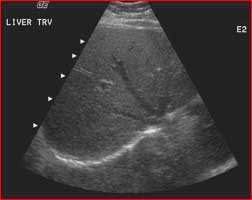

Ultrasound offers images in real time. This means it can show the movement of internal tissues, organs and blood vessels. For example, your physician can see blood flow and heart valve function. It is commonly used for imaging the liver, gallbladder, spleen, pancreas and kidneys.

Ultrasound of the liver